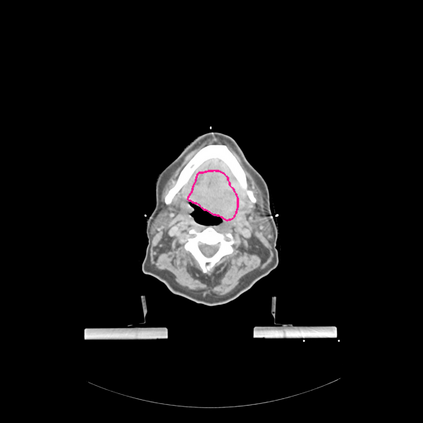

Radiomics uses quantitative medical imaging features to predict clinical outcomes. Currently, in a new clinical application, finding the optimal radiomics method out of the wide range of available options has to be done manually through a heuristic trial-and-error process. In this study we propose a framework for automatically optimizing the construction of radiomics workflows per application. To this end, we formulate radiomics as a modular workflow and include a large collection of common algorithms for each component. To optimize the workflow per application, we employ automated machine learning using a random search and ensembling. We evaluate our method in twelve different clinical applications, resulting in the following area under the curves: 1) liposarcoma (0.83); 2) desmoid-type fibromatosis (0.82); 3) primary liver tumors (0.80); 4) gastrointestinal stromal tumors (0.77); 5) colorectal liver metastases (0.61); 6) melanoma metastases (0.45); 7) hepatocellular carcinoma (0.75); 8) mesenteric fibrosis (0.80); 9) prostate cancer (0.72); 10) glioma (0.71); 11) Alzheimer's disease (0.87); and 12) head and neck cancer (0.84). We show that our framework has a competitive performance compared human experts, outperforms a radiomics baseline, and performs similar or superior to Bayesian optimization and more advanced ensemble approaches. Concluding, our method fully automatically optimizes the construction of radiomics workflows, thereby streamlining the search for radiomics biomarkers in new applications. To facilitate reproducibility and future research, we publicly release six datasets, the software implementation of our framework, and the code to reproduce this study.